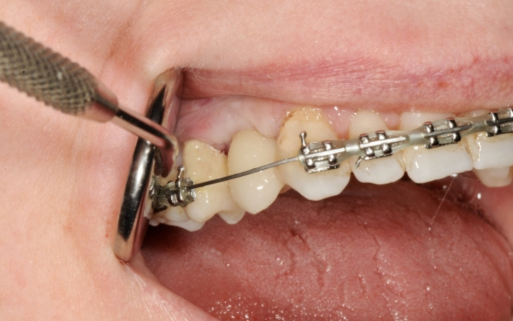

Zajmuję się zarówno wszczepianiem implantów, jak i rekonstrukcją ubytków kostnych, a także podnoszeniem dna zatoki szczękowej, co pozwala na uzyskanie optymalnych warunków do wszczepienia implantów, nawet w przypadku dużych ubytków kostnych.

Założenie jednego implantu trwa średnio 15 minut i zwykle odbywa się przy miejscowym znieczuleniu.

Ze względu na to, że wszczepienie implantu odbywa się przy znieczuleniu miejscowym, zabieg ten porównywalny jest do usunięcia zęba jednokorzeniowego.

Po jego zakończeniu stomatolog najczęściej zaleca terapię antybiotykową, która ma zapobiec infekcji.